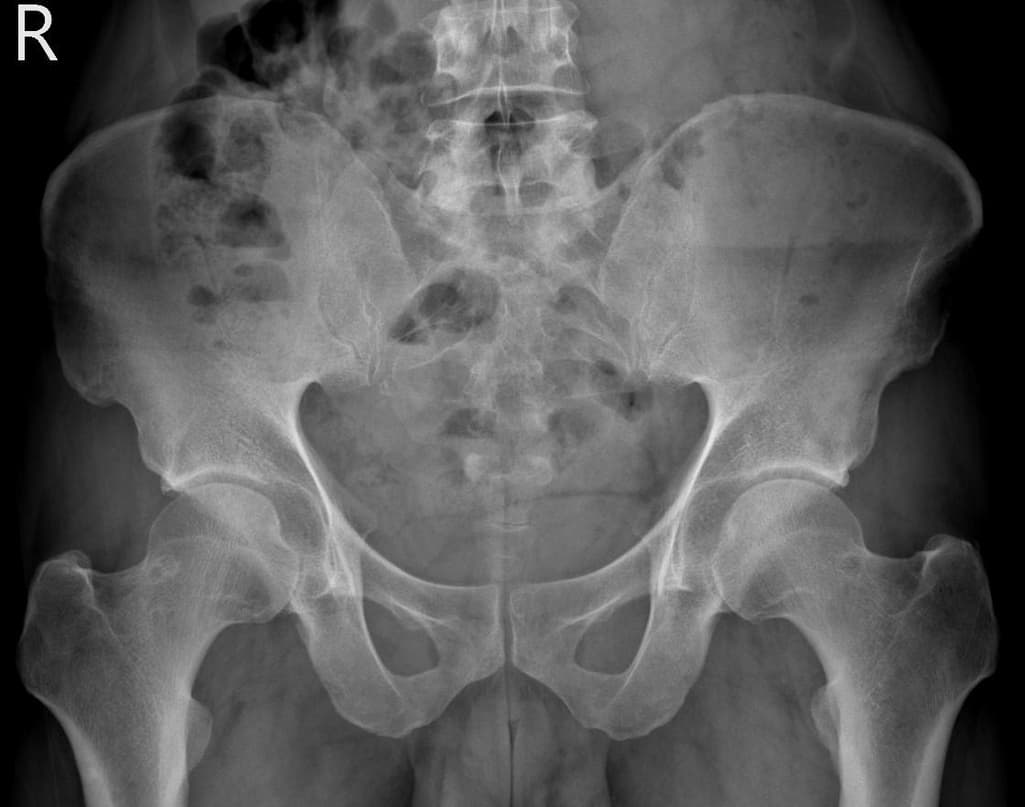

허리랑 고관절 엑스레이사진판독 조언 부탁드립니다

간헐적인 약간의 찌릿 뜨끔 한 오른쪽허리통증이 근한달정도

허리를 굽힌다던지등의 특정자세에 오는것 같진 않습니다

최근 한몇일은 일시적 뻐근한 느낌도 있고요

엑스레이 상에서는 요추 배열이 전반적으로 잘 유지돼 보입니다. 마나 일부 요추 간격이 좁아진 부위가 있어 보입니다. 말씀하신 것처럼 특정 동작에서 찌릿 혹은 뜨끔하거나, 최근 뻐근함이 생기는 건 디스크 초기나 근육, 인대 긴장에서도 나타날 수 있습니다.

허리의 커브가 줄어들어있다는것을 제외하고는 크게 문제가될만한 부분은없는데요 통증과불편감이 지속된다면 MRI와같은 정밀검사가 필요할수있습니다

사진상 요추 사이의 간격이 다소 좁아 보이며 간격이 좁다는 것은 퇴행성 변화를 의미하며 척추의 정렬 또한 큰 전위는 없어 보이나 허리 곡선이 정상보다는 조금 감소한 상태로 이러한 경우 근육의 긴장이나 만성적인 통증이 발생할 수 있습니다.

• 엑스레이 검사를 통해서는 현실적으로 뼈 위주의 평가만 가능하며 정밀하고 자세하게 평가를 내리는 것은 어렵습니다. 올리신 엑스레이 사진들에는 특별히 문제가 있다고 볼만한 소견이 크게 있어보이거나 하지는 않습니다.

우선 현재로썬 척추와 척추 사이인 디스크 공간이 좁지는 않아보이지만 다소 요추의 커브가 감소되어 있어 보입니다.

올려주신 사진에서 크게 특이사항이 보이는 것으로생각되지는 않습니다.

고관절의 구조적인 이상보다는 주변 근육이나 신체기능, 근골격계질환등의 문제로 인해서 통증이 지속될 수 있으므로, 통증이 오래 지속된다면 전문적인 치료를 고려해보시면 좋겠습니다.